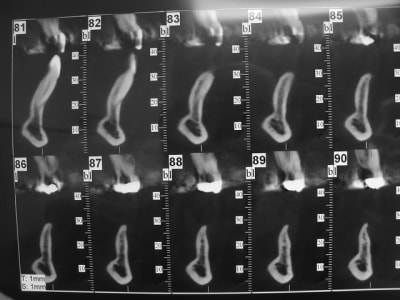

DSC05920_naoih2.jpg